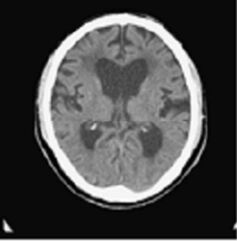

51.65 歲男性走路小碎步,容易跌倒。他的太太表示他最近事情常常記不起來,反應遲鈍,有時也會尿失禁。他的腦部電腦斷層掃描結果如下,如果接受腦室腹腔分流術(ventriculoperitoneal shunt)治療,下列敘述何者最恰當? (A)走路比記憶力容易進步 (B)術前腦壓測量通常不正常 (C)尿失禁最容易進步 (D)手術後進步通常可以持續 5 年以上